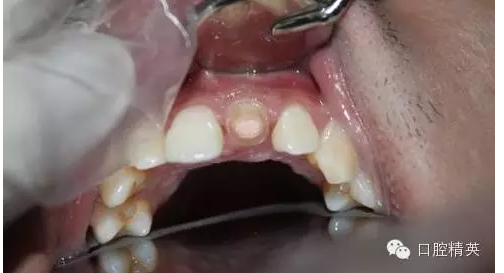

一年輕小伙,在打籃球中,被隊友打斷門牙,來本診所時已經(jīng)露髓,局麻拔髓后,行RCT。后因經(jīng)濟關(guān)系,擬鈷鉻樁加鈷鉻烤瓷冠修復(fù),備牙后才留照片:

1:牙根,備牙后,

2:唇側(cè)觀,